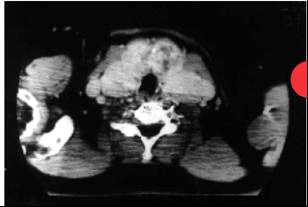

- טומוגרפיה ממוחשבת - בטומוגרפיה ממוחשבת ניתן לראות את גודל הבלוטה, אם קיימים בה נגעים ובמיוחד האם הבלוטה גולשת לתוך המיצר (מדיאסטינום גויטר רטרוסטרנלי) (תצלום 1.14 - 2.14).